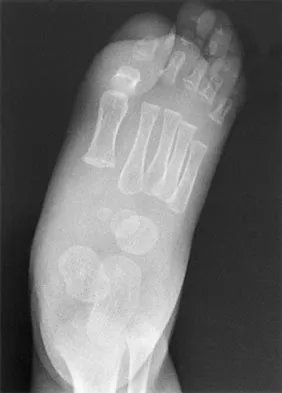

What is the most common malignant tumor of the foot?

Explanation

Whereas chondrosarcoma is the most frequently occurring malignant bone tumor of the foot and synovial sarcoma is the most common soft-tissue foot malignancy, the most common malignant tumor overall is melanoma. It constitutes approximately 25% of lesions found on the lower extremity. Furthermore, 31% of all melanomas arise in the foot. Mizel MS, Miller RA, Scioli MW (eds): Orthopaedic Knowledge Update: Foot and Ankle 2. Rosemont, IL, American Academy of Orthopaedic Surgeons, 1998, pp 11-26.